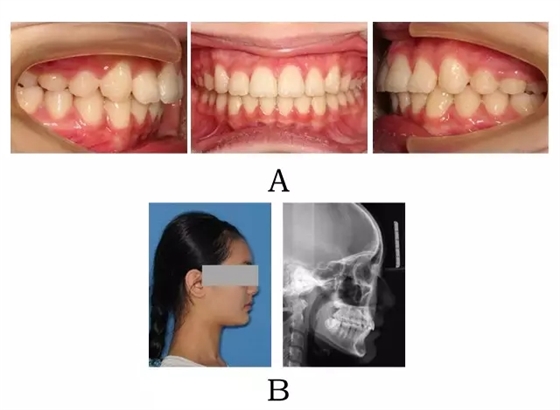

圖3-3:頜位性突面畸形矯形治療臨床療效及頭顱側(cè)位影像變化。

(A) 咬合改善 (B) 側(cè)貌改變

Figure 3-3. Treatment outcomes for mandibular positional prognathism. (A) Occlusion correction. (B) Facial esthetic improvement.